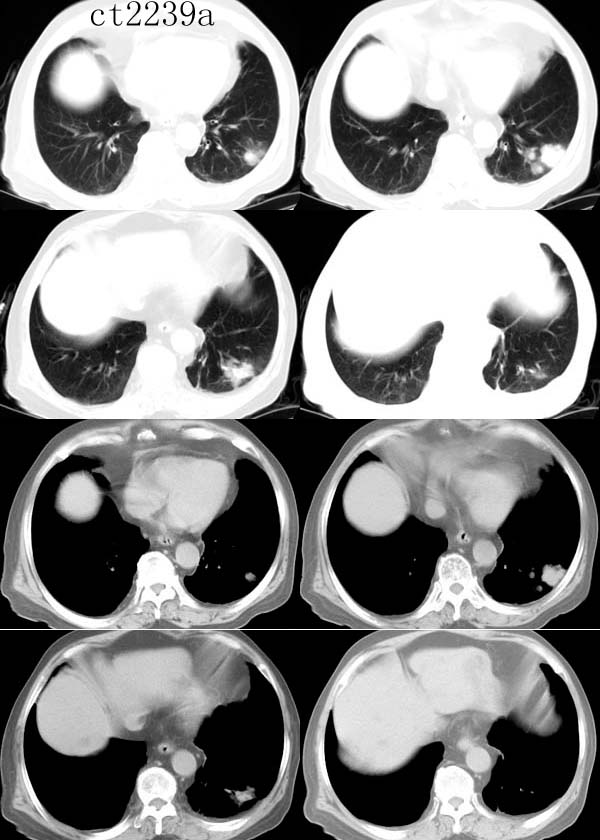

球形肺炎:病变密度相对较淡,中央密度略高,ct图片上密度较为均匀,增强中央可出现无强化区。病变邻近胸膜反应较为显著,可表现为增厚、粘连(可以比较广泛),病变内可以见到大血管的贯穿,周围及近肺门侧可以见到血管纹理增多、增粗,可有支气管充气征象,两侧可垂直于胸膜或呈方形,边缘可为刀切征,它可以出现毛刺样的类似改变,短期内抗炎治疗有效。

炎性假瘤:病灶可呈圆形、椭圆形、三角形、亚铃形等,边缘多比较光滑,密度呈中或偏高密度,周围可有不规则条索影,周围一般无周围充血征象。肿块内可有空洞,可有钙化,但多密度均匀。假性淋巴瘤型可见支气管气相,多为单发,少见多发。肿瘤生长慢,可持续十余年,抗炎可有效果,但阴影不易消散。